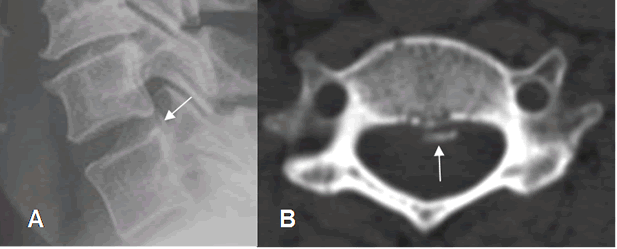

Las calcificaciones del disco son densas en Rx y TAC. Dependiendo del tipo y concentración de calcio, en algunos casos las calcificaciones se identifican como zonas con aumento de la señal en T1. (4). (Fig 36, 37 y 38).

Fig 37. Calcificación del disco.

A: TAC axial y B: TAC reconstrucción sagital. Calcificación alargada, en la parte derecha del disco.

Fig 38. Calcificación del disco.

A: Rx lateral y B: TAC axial. Calcificación en el borde posterior del disco.